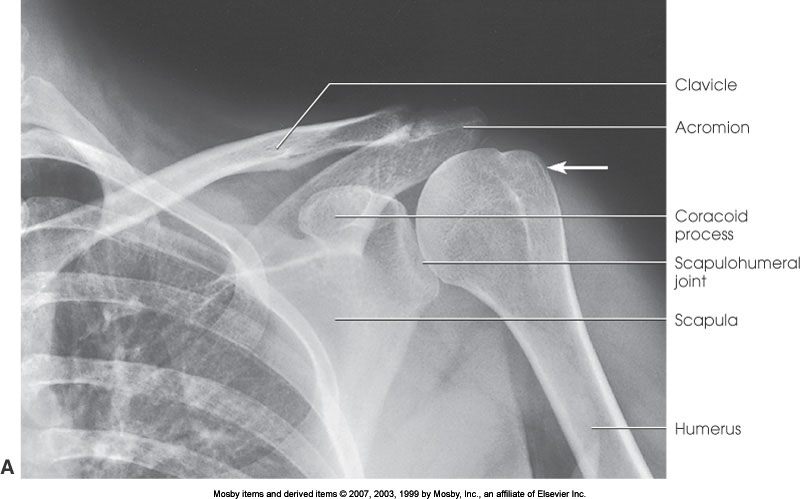

AP Shoulder (External Rotation)

What position is demonstrated?